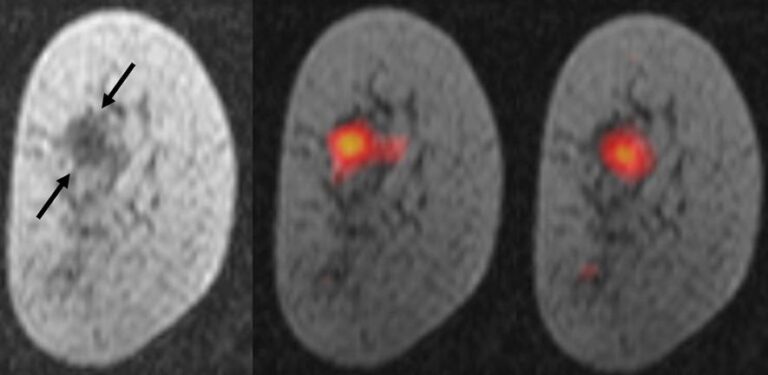

Magnetized molecules help see breast cancer more clearly